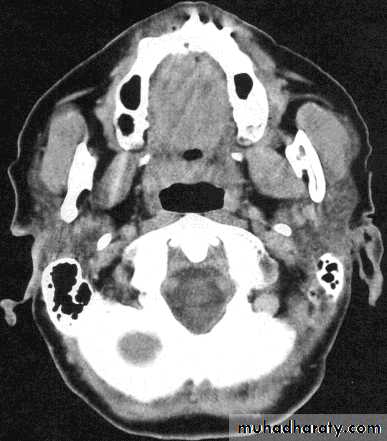

ComparisonsMRI image

CAT image

head

Compare bone and soft tissue density